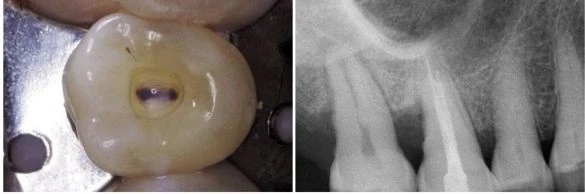

Buồng tủy của răng cối nhỏ thứ nhất hàm trên được định hướng theo chiều ngoài trong. Trong đa số các trường hợp chúng có hai sừng tủy -tương ứng cũng có hai ống tủy – bên dưới các múi răng (hình 11.43). Hướng của xoang tủy vì vậy cũng theo chiều ngoài trong, không phải là gần xa như trong tạo xoang trám.

Hai sừng tủy nằm trong đỉnh của múi tương ứng. Miệng của hai ống tủy cũng gần như nằm tương ứng với sừng tủy. Vì vậy, nhìn chung ta có thể sửa soạn một xoang tủy tốt mà không phạm đến múi răng. Điểm đi vào của mũi khoan là phần giữa rãnh trung tâm (hình 11.44 A), và khoan theo hướng song song với trục của răng (hình 10.44 B, C).

Hình 11.43. Răng cối nhỏ thứ nhất hàm trên cắt theo chiều dọc, thấy hình ảnh sừng tủy và miệng ống tủy.

Hình 11.44. A. Mặt nhai của răng cối nhỏ thứ nhất trên. B. Mũi khoan kim cương tròn xuyên qua phần giữa rãnh trung tâm, phá vỡ trần buồng tủy. C. Hình ảnh X-quang. D. Đưa mũi khoan đã dùng trước đó vào lỗ đã được mở ở giai đoạn xuyên qua, trên đường đi ra, chạy mũi khoan để lấy đi những phầncòn lại của trần buồng tủy. E. Hình ảnh X-quang (còn tiếp).

Khi xuyên qua với một mũi khoan kim cương tròn và tay khoan siêu tốc, cần kết hợp chuyển động mũi khoan theo chiều ngoài trong để phát họa đường viền mặt nhai của xoang tủy. Cần ghi nhớ rằng: trong giai đoạn xuyên qua, mũi khoan không nên tạo một xoang tủy dạng ống với các thành song song, mà nên kết hợp với chuyển động xoắn ốc để tạo hình dạng phễu khi khoan xuống lớp ngà. Khi đã xuyên vào đến buồng tủy, sử dụng tay khoan chậm để lấy phần ngà còn lại sau giai đoạn xuyên qua (hình 11.44 D, E).

Dùng mũi khoan đầu trơn với tay khoan siêu tốc tạo hình dáng của xoang mở tủy ở giai đoạn hoàn thành và làm loe (hình 11.44 F,G). Hình dạng của xoang mở tủy khi hoàn thành có hình trứng với đường kính lớn hơn theo chiều ngoài trong và nó thường không liên quan đến đỉnh múi (hình 11.44 H, I). Việc nó có liên quan đến đỉnh múi hay không tùy thuộc vào góc phân kỳ giữa hai chân răng và của hai ống tủy: nếu càng phân kỳ thì xoang tủy càng nhỏ, nếu càng song song thì xoang tủy càng có khả năng phạm đến múi răng. Hai ống tủy thường giao nhau tại một rãnh cạn, ta có thể xác định được rãnh này nếu kiểm tra kỹ sàn buồng tủy (hình 11.45).

. Hình 11.44. (tiếp theo) F. Dùng mũi khoan kim cương ở giai đoạn hoàn thành và làm loe. G. Hình ảnh X-quang của giai đoạn hoàn thành và làm loe. H. Xoang tủy đã hoàn thành. I. Hình ảnh X-quang: múi vẫn còn nguyên.

Hình 11.45. Miệng của hai ống tủy của răng cối nhỏ thứ nhất trên thường giao nhau bởi một rãnh trên sàn tủy.